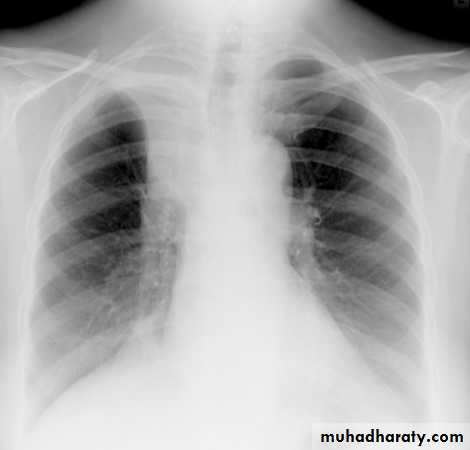

chest X-ray